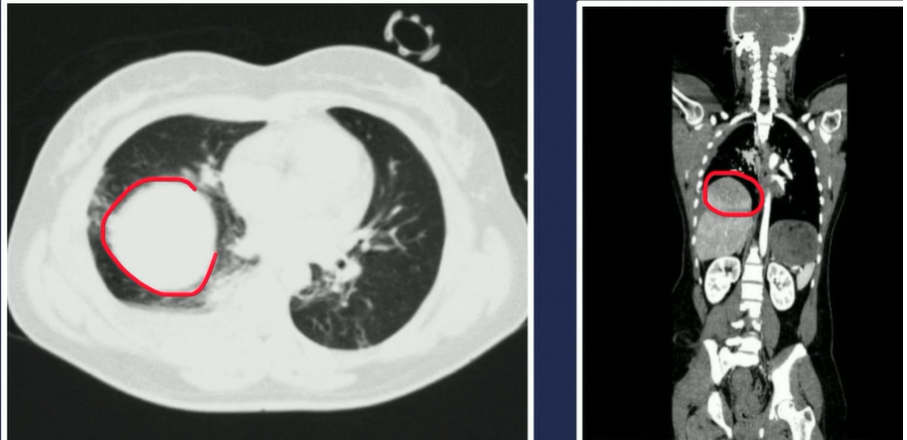

Hérnia diafragmática traumática

Definição e conduta

imagem 1

A

• Hérnia diafragmática provocada por traumas, como uma lesão abdominal fechada

• Se na direita, há poucas chances de estruturas abdominais herniarem devido ao fígado tamponar

• Todavia, em casos muito extremos (imagem 1), mesmo que se na direita, deve-se fazer laparatomia